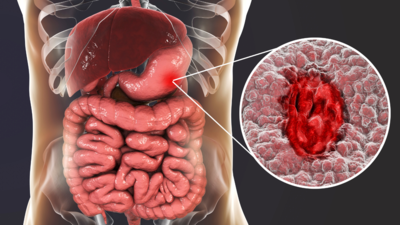

This additive is known as “Maltodextrin”, a polysaccharide derived from starch hydrolysis and is used as a thickener and filler in processed food.Maltodextrin is inert and generally is regarded as safe by the US Food and Drug Administration. However, multiple recent studies have shown detrimental roles played by maltodextrin in the intestinal environment, suggesting that this broadly used food additive may play a role in the rapidly increased incidence of chronic inflammatory disorders, such as inflammatory bowel disease and metabolic syndrome. Maltodextrin is a carbohydrate made from corn, rice, and potato starch, often used in foods to increase their shelf life and make gravies thicker.What do the studies indicateA recent study published in Cellular and Molecular Gastroenterology and Hepatology reveals how Maltodextrin consumption may trigger or worsen intestinal inflammation, determined by using 2 different models of colitis. Such detrimental effects of maltodextrin were linked to activation of endoplasmic reticulum stress and subsequent alterations of the protective mucus layer.

The team of researchers employed distinct experimental models of colitis, inflammatory bowel conditions commonly studied in mice, to assess the effects of Maltodextrin. The study found that

- Chemically induced colitis, is where it mimics inflammatory damage similar to human Inflammatory bowel disease

- Genetically susceptible mice, which are prone to develop intestinal inflammation.

In both of these scenarios, mice were fed diets with varying concentrations of maltodextrin over a set period.

With the subsequent increase in the dosage levels of maltodextrin intake, the intestinal inflammation worsened. Meaning, the more maltodextrin that went inside the mice, the more severe the inflammation became.

The study also assessed its effects on the inner lining of the gut wall. It showed that maltodextrin can promote harmful bacterial behavior, such as biofilm formation by Crohn’s-associated E. coli.